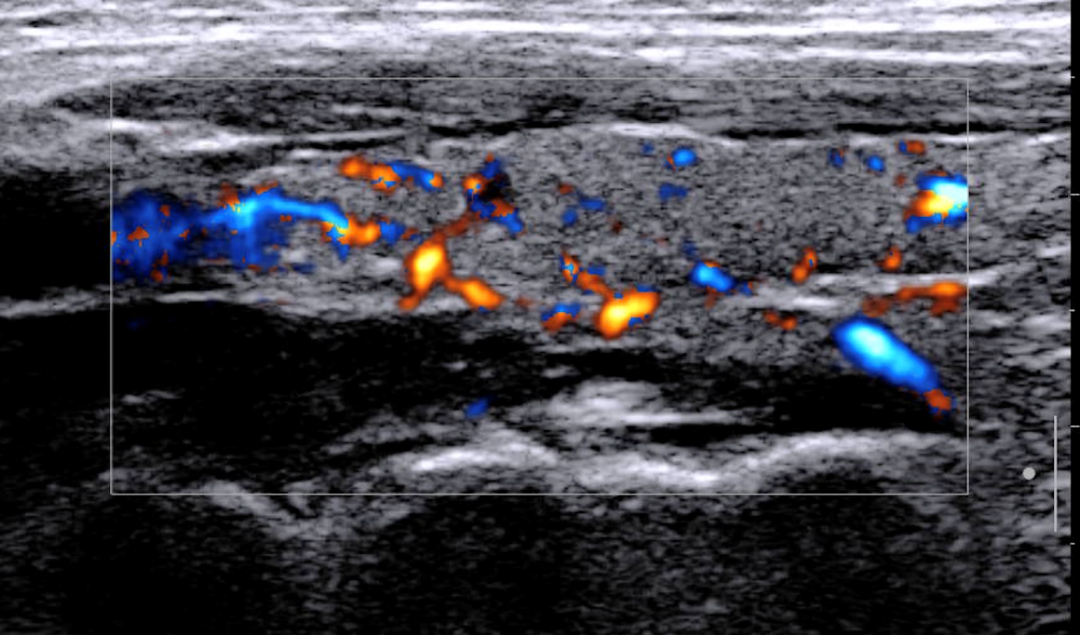

揭示肌肉疼痛之谜:RTSWE---肌筋膜疼痛综合征的福音?

发布时间:2025-01-17

揭示肌肉疼痛之谜肌筋膜疼痛综合征(Myofascial Pain Syndrome)在快节奏的现代生活中你是否也常感受到颈痛、背痛、腰痛等身体各部位的疼?让我们一起揭开肌筋膜疼痛综合征神秘面纱 01. 肌筋膜疼痛综合征(MPS)是什么?肌筋膜疼痛综合征(Myofascial Pain Syndrome,MPS)是由肌肉......